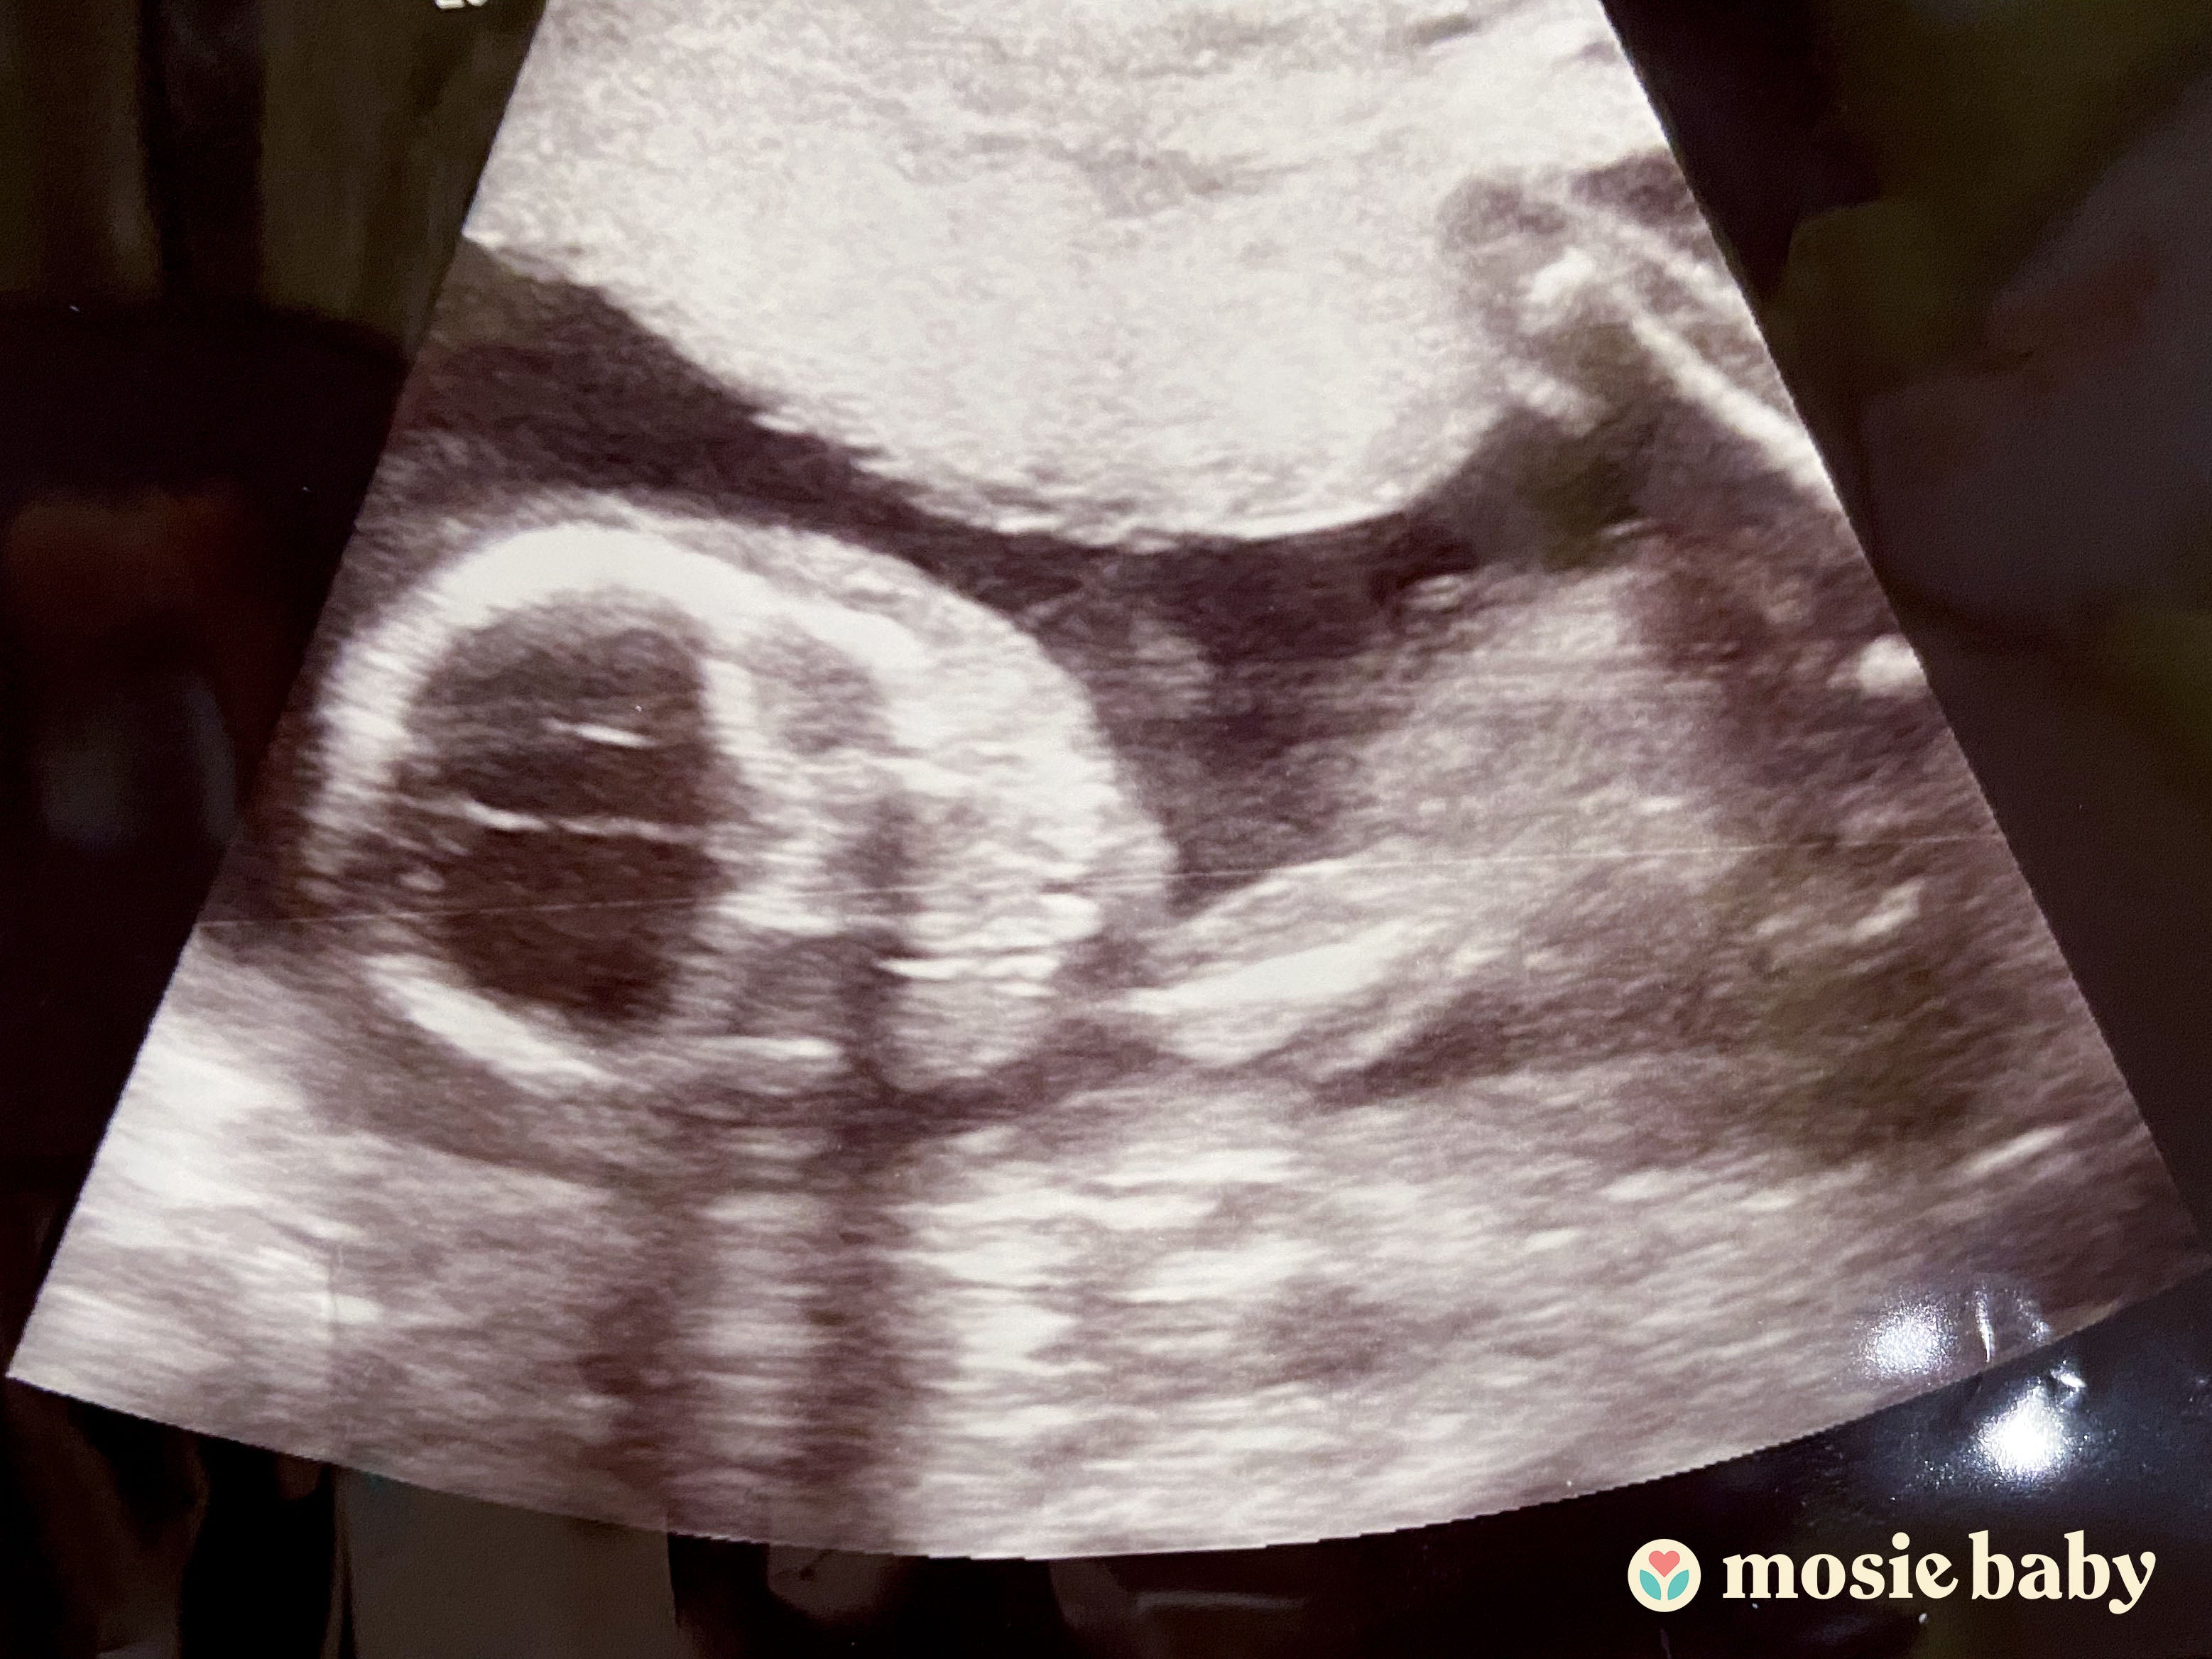

As of today I am 21 weeks pregnant. From the bottom of my heart, I want to thank you all for making this product. I would love to share a little about me and my journey with Mosie Baby. Since childhood I was a shy person and it took me 30 years to make an OBGYN appointment. I know it must be sounding so odd. I made my first appointment when we couldn’t get success having a baby or to be frank making those beautiful moments after marriage, which should be easy for most people. I was told that I have vaginismus, and it might require IUI or similar treatment in order to have that little bundle of joy.

I was always tracking my ovulation cycle using an application, so I knew that I am very much fertile and have no other problem. We were about to schedule an appointment to start the IUI process and that same day I came across the Facebook page of Mosie Baby. I told my husband, let’s give it a try one time before we book an appointment. He ordered two kits with overnight shipping as I was ovulating as per the app in the next couple days. The package arrived immediately despite the current pandemic situation. We tried next day and night. To be frank, we didn’t know how it would work and whether it actually gave us any result. It’s been 7 years since our marriage, and we started planning for a baby about a year ago, but due to my vaginismus it was not so successful through natural means. I was so happy that using Mosie Baby was so easy and gave me confidence that vaginismus is not any physical problem,but it’s more of a psychological problem in my case; where I had fear of losing control over my body. Mosie Baby gave me that comfort and control which was in my hand.

The following week after trying with Mosie Baby, I was feeling happy just because I was able to use it successfully the first time without any pain or fear. So we ordered more kits and planned to use them for a couple months. However, we never had to use the new arrived kits as after three weeks, I missed my period date and guess what...I was pregnant. I am not able to express how I felt looking at those two lines. It took me nine more pregnancy test kit purchases to be convinced that I was actually pregnant. 🥰 I booked my doctor’s appointment and he was so surprised as he was not aware about Mosie Baby. He is the best doctor I could have ever imagined for me. So thankful to him keeping patience with me and blessed to have Mosie in my hand from you guys. Never ever imagined that one try with Mosie Baby was all it would take. My doctor said, I am going to let all my other patients know about it who are planning for IUI to give Mosie Baby a try. So, once again, thank you so much to you who invented this and your entire team who made it possible to deliver in my hand safely and on time.